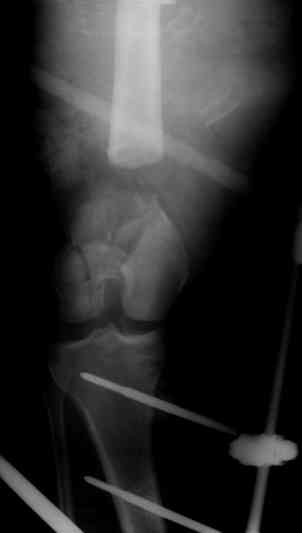

Коллеги! Прошу совета, какую тактику избрать при лечении.Больной 27 лет, мотоциклист. Поступил 23.04.10 ДЗ. О. перелом н.з левого бедра Gustillo 3b (c повреждение бедренной вены), О.Правого бедра Gustillo 2, з. фрагментарный перелом левой голени.При поступлении Hb 66 ISS 40, Фиксация стержневыми аппратами, сосудистые хирурги выполнили шов вены. Выполена резекция бедренной кости 9 см. На 7 сутки Желудочно-кмшечное кроветечение из стрессовых язв, 12 сутки флотирующий тромтоз 14 см установлен кава-фильтр. На 15 сутки закрытие ран местными тканями. Раны заживают первично. Воспаления на стержнях нет. В настоящий момент планируем. Переход со стержневых аппаратов на стержни с антибактериальным покрытием на правом бедре и левой голени. Левое бедро планируем продолжить фиксировать в стержневом аппарате.

Вопрос: что делать с левым бедром? Учитывая внутрисутавной характер перелома, дефект бедра 9 см.

На левом бедре оставили аппарат бедро-голень.

Как вы думаете если сделать следующее.

После заживления раны на левом бедре. Выполнить открытую реподицию и синтез пластиной для дистального бедра. Пластину в проксимальном направлении зафиксировать монокортикально.

А затем выпонить остеотомию бедра в верхней трети.

И тракцию бедра на стержне. Типа (СМ картинки).

После выращивания регенерата стержень блокировать.